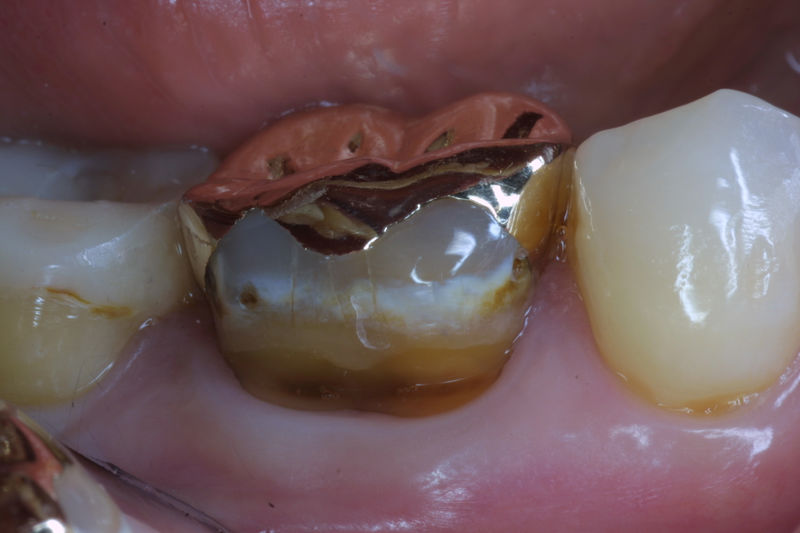

La restauración de un diente tras una endodoncia, es crucial para su supervivencia a largo plazo, ya que el procedimiento puede debilitar la estructura dental. El tipo de restauración elegido depende principalmente de la cantidad de estructura dental remanente después de la endodoncia. Principalmente se usan incrustaciones, coronas y/o postes.

Restauraciones fabricadas en el laboratorio con materiales estéticos, los cuales cubren de manera parcial dientes posteriores. Se utilizan primariamente para restaurar dientes con caries, fracturas y/o defectos amplios. Para poder enviar el caso al laboratorio se toman impresiones utilizando materiales de impresión o técnicas modernas digitales.

Restauraciones fabricadas en el laboratorio con materiales estéticos, los cuales cubren de manera total dientes anteriores y posteriores. Se utilizan primariamente para restaurar dientes con caries, fracturas y/o defectos amplios, así como soportes de puentes. Para poder enviar el caso al laboratorio se toman impresiones utilizando materiales de impresión o técnicas modernas digitales.

Son aditamentos artificiales colocados en la parte interna de la raíz de dientes con tratamiento endodóntico y con amplia destrucción. Usados comúnmente para soportar coronas completas.